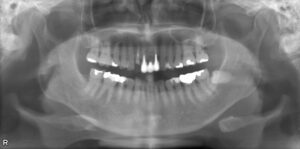

• 上顎オールオン6/下顎ロケーター義歯 症例

BEFORE AFTER 72歳女性/上顎6本・下顎2本 【治療内容】 上下顎ともに骨吸収が進み、入れ歯が合わなくな…